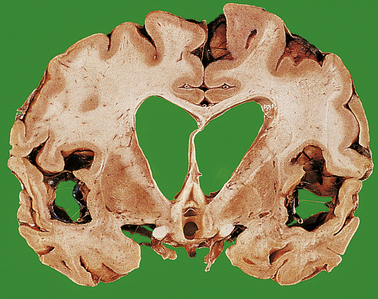

At a very early stage after cerebral infarction, no naked-eye abnormalities are apparent. However, 24 hours after infarction the affected tissue becomes softened and swollen, with a loss of definition between grey and white matter. There may be considerable oedema around the infarct, resulting in a local mass effect. Within 4 days, the infarcted tissue undergoes colliquative necrosis. Histology shows infiltration by macrophages, which are filled with the lipid products of myelin breakdown. Reactive astrocytes and proliferating capillaries are often present at the edge of the infarct. Eventually, all the dead tissue is phagocytosed to leave a fluid-filled cystic cavity with a gliotic wall (Fig. 26.10). Some infarcts are haemorrhagic, possibly due to reflow of blood through anastomotic channels. Anterograde degeneration of nerve fibres occurs distal to the site of infarction, for example in the ipsilateral cerebral peduncle in infarcts involving the internal capsule.

image

Fig. 26.10 Cerebral infarct: cystic change. In this old infarct in the territory of the right middle cerebral artery, the necrotic tissue has been phagocytosed to leave a cystic cavity lined by glial tissue.